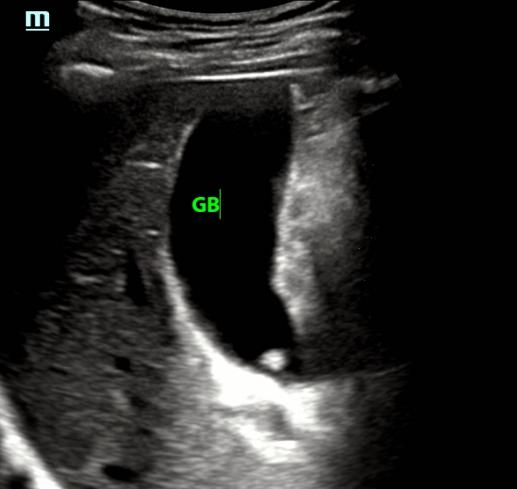

一边心想,一边让李四左侧卧位,从肋间看看胆囊

肋间明显看胆囊好点了,但胆囊颈部还是显示不清。。。。